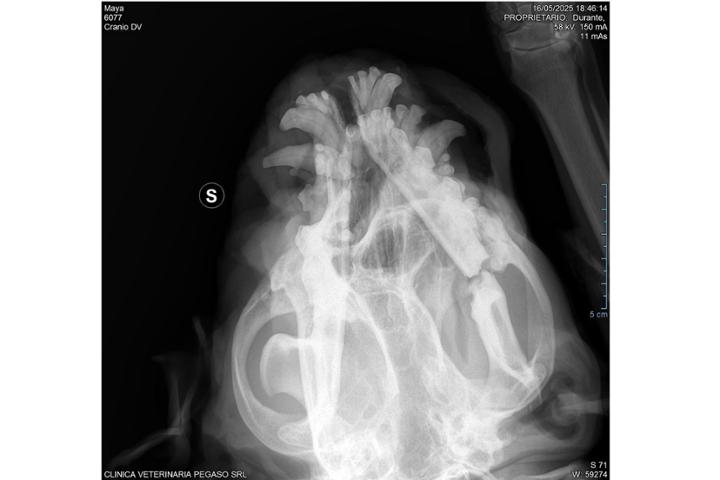

Abbiamo ricostruito la mandibola con una protesi ad un cane abbandonato e investito in strada. L'abbiamo chippata e chiamata Maria, aveva anche altre fratture alle costole, l' abbiamo curata per la leishmaniosi e ha subito 4 interventi; tac, esami post interventi, radiografie analisi del sangue e un mese di ricovero in clinica oltre ai numerosi farmaci che tuttora assume. Le donazioni sono essenziali perché le spese sono ingenti.